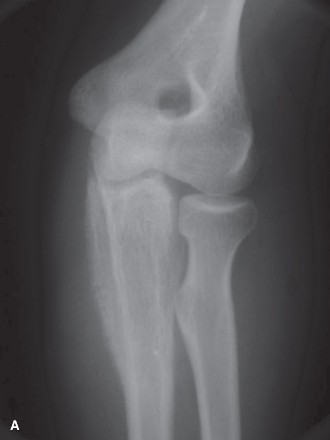

A 13-year-old male presents to your clinic with 2 to 3 months of progressive pain in the elbow, as well as sw…